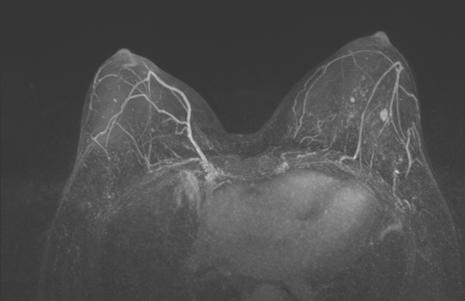

图3. 上图为治疗前,下图为治疗6周期后

治疗6个周期后,乳腺增强MRI显示靶病灶明显缩小,临床疗效评估为PR;腋窝靶病灶消失,临床疗效评估为CR。

新辅助治疗期间采用乳腺核磁评估疗效,6周期治疗后肿瘤退缩良好,乳腺增强MRI显示靶病灶明显缩小,临床疗效评估为PR;腋窝靶病灶消失,临床疗效评估为CR。同时术后病理显示该患者病灶中无浸润性癌成分残留,Miller-Payne分级为G5,腋窝淋巴结无癌残留,达到pCR。鉴于HER2阳性乳腺癌侵袭性强、预后不良,抗HER2治疗都应该贯穿始终。所以对于新辅助治疗后达到pCR的患者,指南推荐继续应用双靶治疗。内分泌治疗的选择上考虑到患者为绝经前女性,术前T3及腋窝淋巴结转移等高危因素,根据指南推荐,应用了OFS+AI的治疗方案。